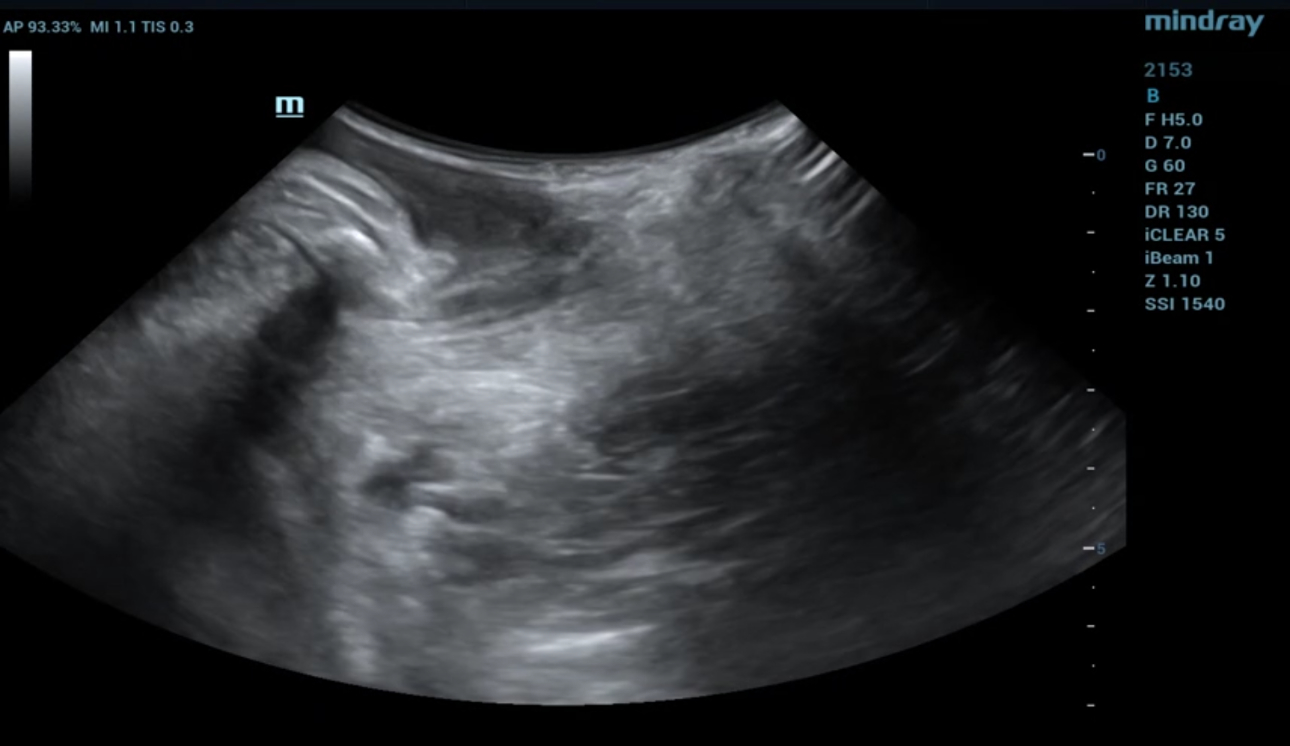

?? ?? ????? parasagittal view??? ???/?? 2D ???, 3D/4D ?? ??, Ipage+?? ?? ?? ?? ???? ?????.

?? 39??? 30???(G1P1)?? ??? Negative-pressure vacuum extraction? left perineotomy? ?????, ???? ???? 3.387kg?????. Pelvic floor ???? ?? 42? ? ???????.

- 2D ?? : ???? ??? ?? ?? ???? interruption? ?? ???? ??? ?? ??? ??.